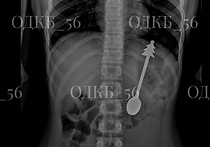

В Оренбурге врачи спасли ребёнка с 14-сантиметровой ложкой в желудке